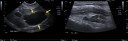

RadioQuiz 41: Une masse pancréatique ?